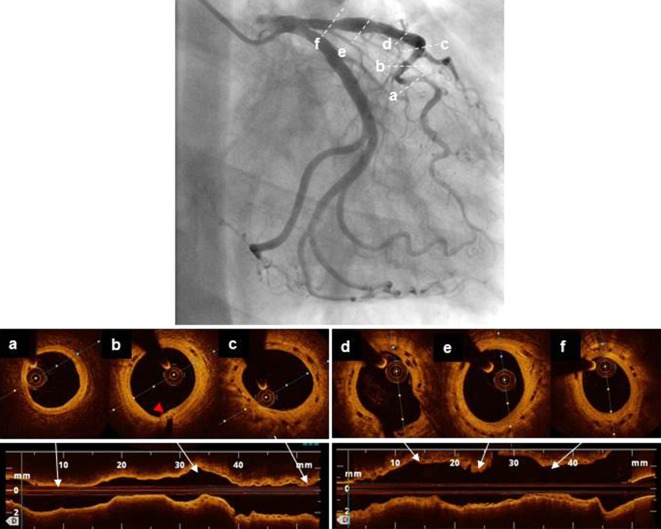

Fig. 4.

Follow-up angiogram and optical coherence tomography (OCT) 2 years after treatment of the in-scaffold restenosis. a is done in a zone of muscular bridging showing the absence of significant stenosis in that area. The red arrowhead shows the metallic marker of the distal implanted scaffold. The favorable evolution with disappearance of the neointimal damages caused by the scoring balloon is clear in the OCT images b–f, which also show partial resorption of the scaffold struts